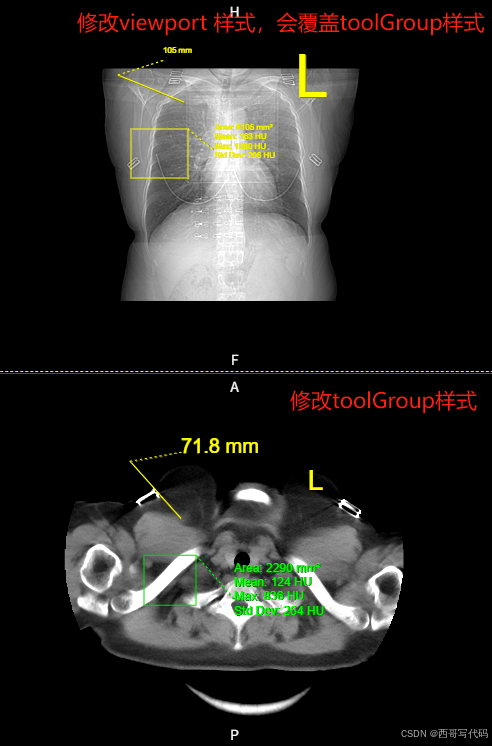

基于cornerstone3D的dicom影像浏览器 第二十八章 LabelTool文字标记,L标记,R标记及标记样式设置

文章目录 前言一、L标记、R标记二、修改工具样式1. 样式的四种级别2. 导入annotation3. 示例1 - 修改toolGroup中的样式4. 示例2 - 修改viewport中的样式 三、可配置样式 前言 cornerstone3D 中的文字标记工具LabelTool,在添加文字标记时会弹出对话框让用户输入文字…...